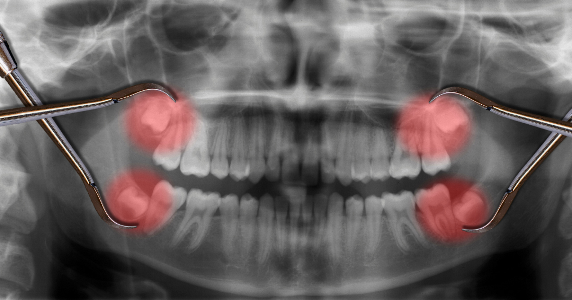

Зубы мудрости – это рудимент. Они достались нам «по наследству» от далеких предков, которые ели более грубую пищу. Их зубы были крупнее, а челюсти – больше.

Сегодня в 90% случаев зубы мудрости требуют удаления, если:

• Зуб не прорезывается полностью – воспаляется десна.

• Зуб растет неправильно, в сторону, в щеку, в соседний зуб.

• Слишком крупные размеры.

• Эстетические проблемы – смещает остальные зубы.